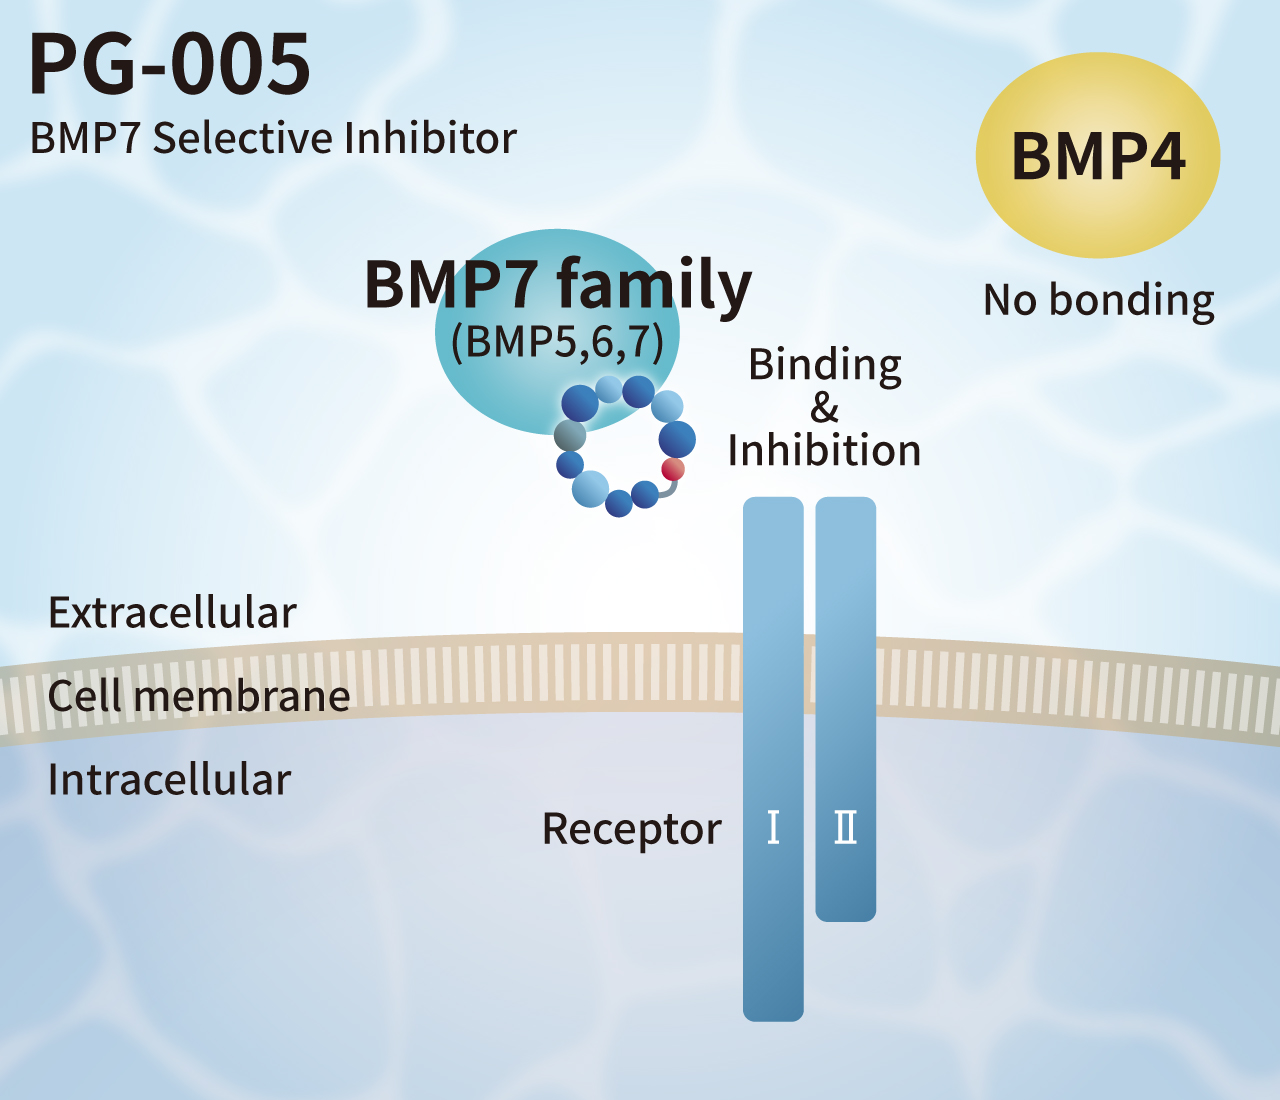

Currently, FBS and recombinant growth factors are used for cell culture. However, such products have some challenges such as variation in quality among production lots, contamination by biological impurities, low stability, and extremely high prices.